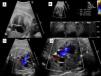

We found evidence of premature constriction of the ductus arteriosus in 7 pregnant women, all of who were diagnosed in the third trimester at a mean gestational age of 35.4 weeks. Table 1 shows the characteristics of the pregnant women. The outcomes were favourable when the triggering factor was removed (5/7). One of the foetuses had a severe restriction of blood flow through the ductus arteriosus with dilation and dysfunction of the right heart chambers and severe tricuspid regurgitation (Fig. 1) that persisted in the neonatal period and was observed to have normalised in subsequent follow-up office visits.

Severe premature constriction of the ductus arteriosus. (A) Four-chamber view showing dilatation of the right heart chambers with the foramen ovale flap bulging into the left atrium. (B) Doppler of the ductus arteriosus revealing a continuous blood flow with increased systolic and diastolic flow velocities. (C) Severe tricuspid regurgitation. (D) Three-vessel view showing a reduced ductal diameter.